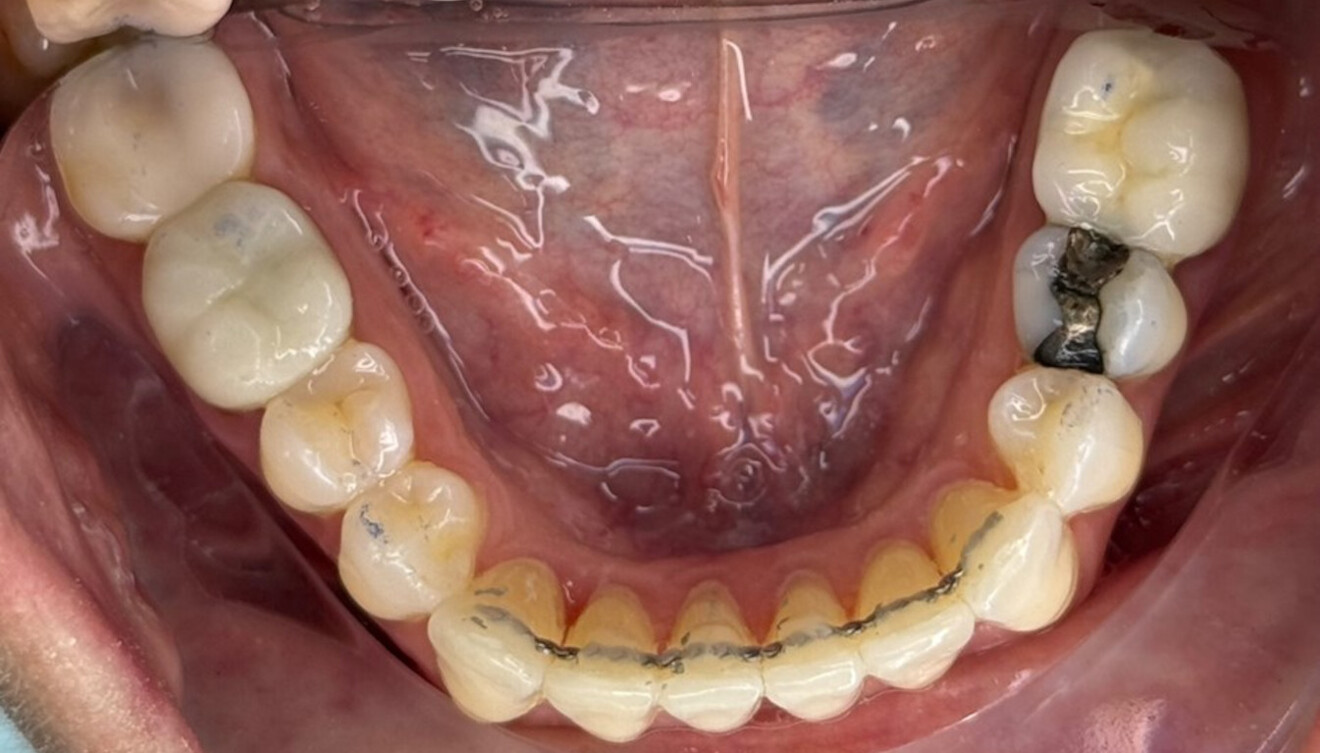

Fig. 4: Intra-oral pre-treatment photograph.